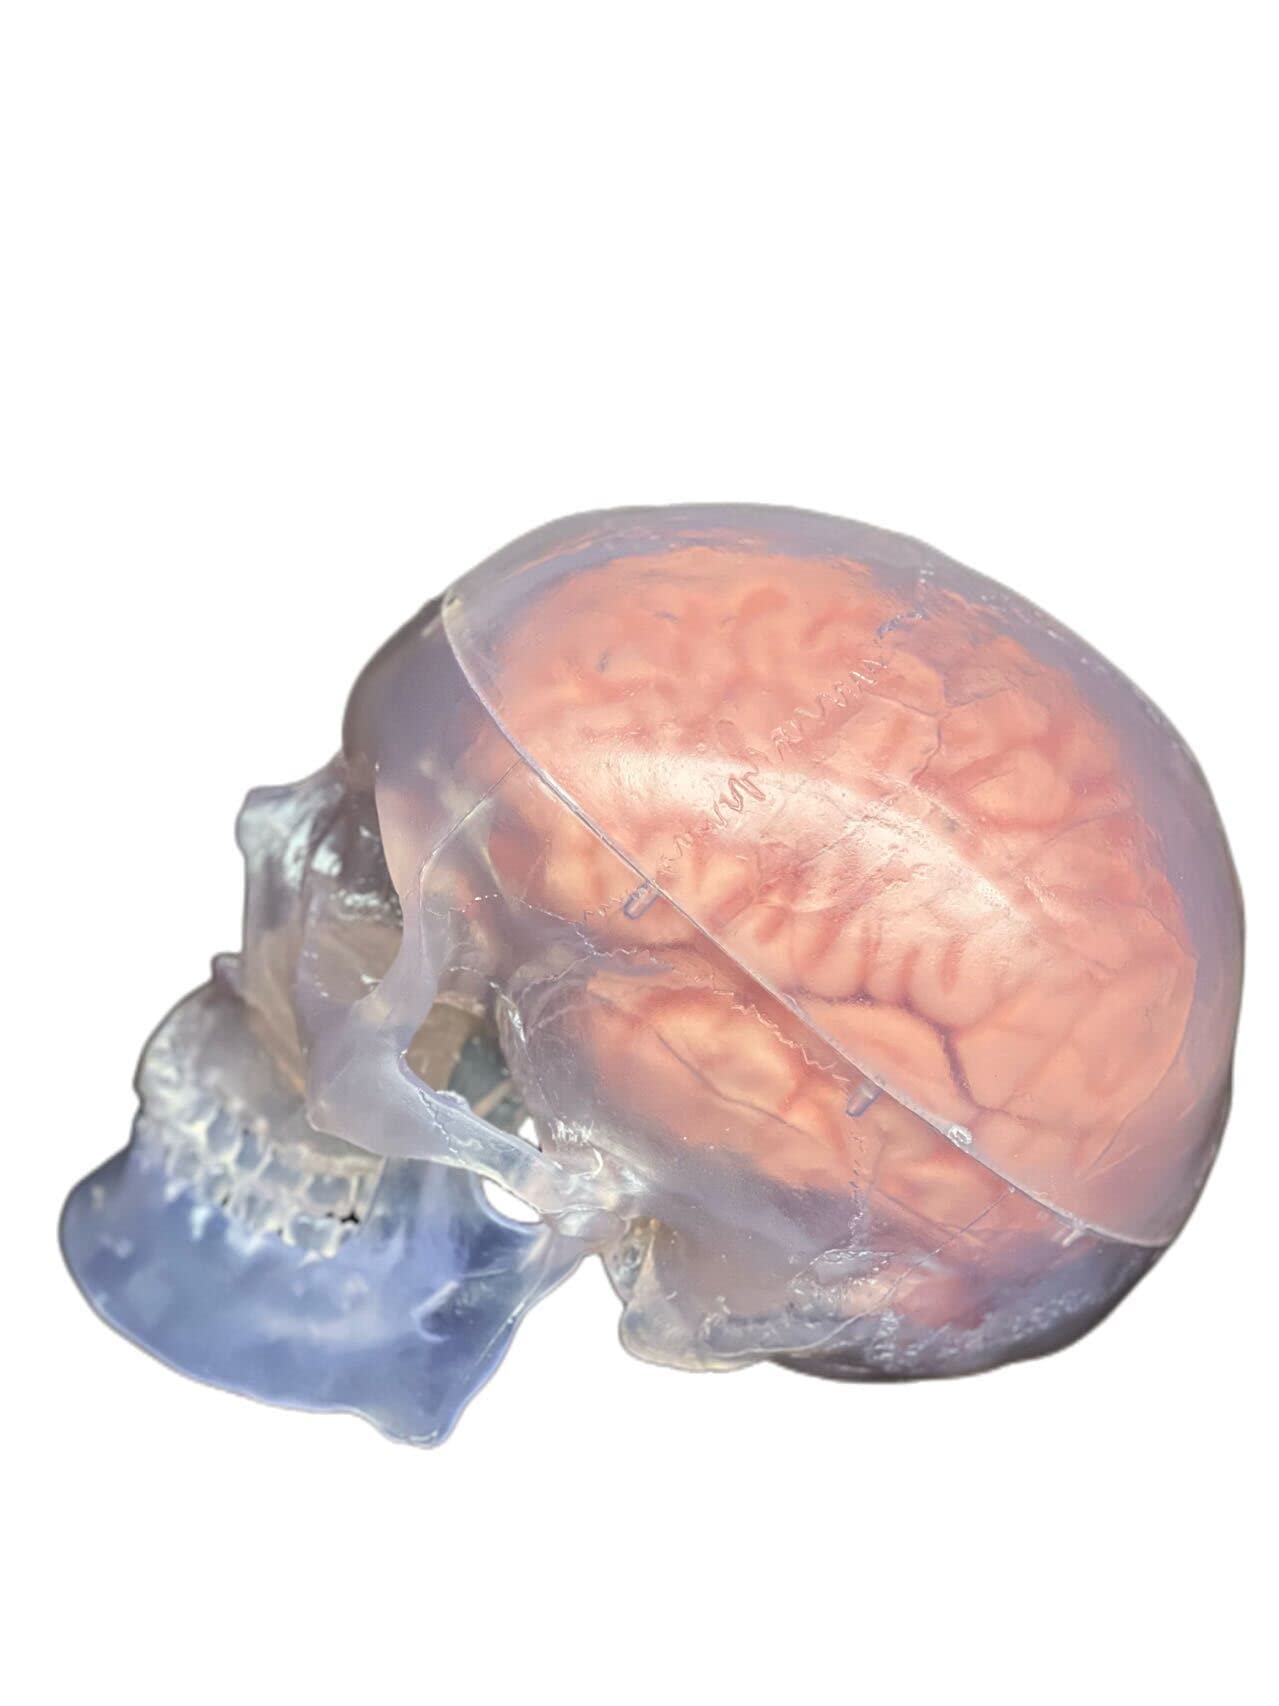

This model is cast from a high-quality original specimen. The classic skull is medically detailed in structure. It has highly accurate representation of the fissures, foramina, processes, sutures etc. Skull is 3-part: Skull Cap, Base of Skull and Mandible. The mandible is articulated on springs to demonstrate natural movements. Use this unique transparent replica of the human skull to study internal structures that otherwise are visible only through x-ray images. Brain separates into 8 parts: frontal and parietal lobes (2), temporal and occipital lobes (2), medulla (2), cerebellum (2). Structures are shown in great detail with about 30 features marked with numbers. Number key is provided. A great addition to any educational collection. Size: Life size Measurement: 22X13X17cm Weight: 2 kgs Material: high quality PVC

- The skull is 3-part: Calvaria, Base of Skull, and Mandible.